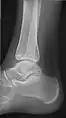

• Ankle - AP/Mortice and Lateral